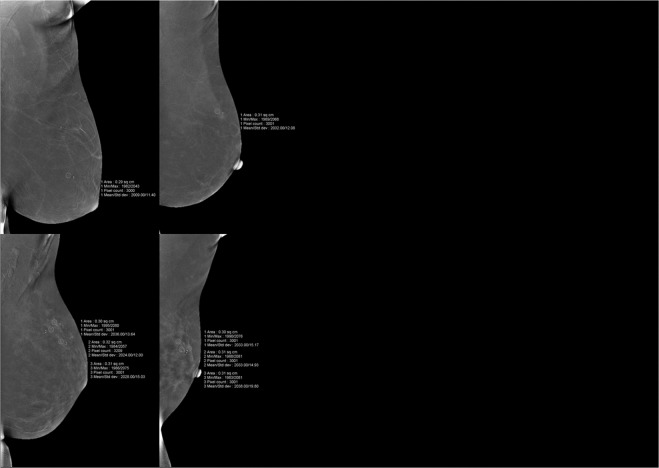

BPE—The extent of BPE was categorized subjectively using both CC and MLO views. In the absence of a recognized CESM lexicon, the volume and intensity of enhancement were categorized according to the BI-RADS MRI grading system as: level a = minimal; level b = mild; level c = moderate; level d = marked (Fig. 1). The intensity of enhancement was measured quantitatively using a region-of-interest (ROI) of about 0.3 cm2 placed manually over the area with the most enhancement within the BPE on the last MLO image, while avoiding blood vessels and the pectoralis major muscle. The maximum, minimum, and difference pixel values were recorded. For BPE level (see below) a and b subjects, the ROI was placed three times at the area with most obvious BPE; for level c and d subjects, the ROIs were placed at three areas with obvious BPE (Fig. 2). For subjects with lesions encountered incidentally on the last MLO image, the area for BPE measurement was selected so as to avoid abnormal enhancement around the lesion or more than 1 cm from the lesion (Fig. 3). For lesions observed on ultrasound but not on CESM, the ROI was not placed at the location of the lesion on ultrasound.

Figure 1.

Examples of ROI measurement for each level of BPE: (a) minimal = a, (b) mild = b, (c) moderate = c, and (d) marked = d.